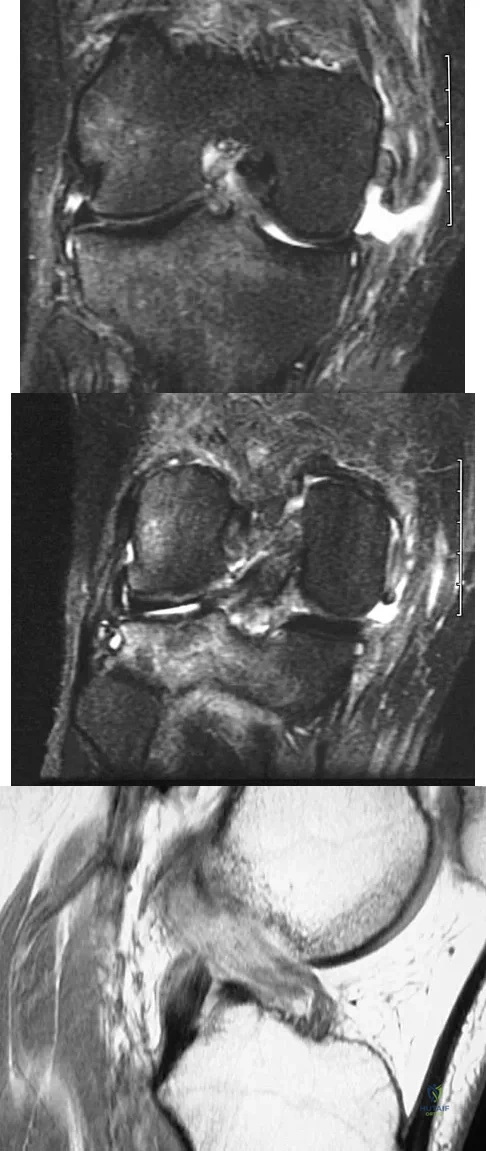

A 21-year-old man has had right groin pain for the past year. A radiograph, CT scan, MRI scans, and a biopsy specimen are shown in Figures 50a through 50e. What is the most likely diagnosis?

The pathology demonstrates a very cellular chondroid matrix with multinucleated forms, atypia, and myxomatous regions. This is most consistent with a myxoid chondrosarcoma. The radiograph shows a well-circumscribed lesion in the superior and medial aspect of the right acetabulum. The CT and MRI scans confirm these same findings with no evidence of matrix mineralization or significant surrounding edema. Unfortunately, in this location with this appearance, the radiographic differential diagnosis includes all the diagnoses listed. Terek RM: Recent advances in the basic science of chondrosarcoma. Orthop Clin North Am 2006;37:9-14. Donati D, El Ghoneimy A, Bertoni F, et al: Surgical treatment and outcome of conventional pelvic chondrosarcoma. J Bone Joint Surg Br 2005;87:1527-1530.